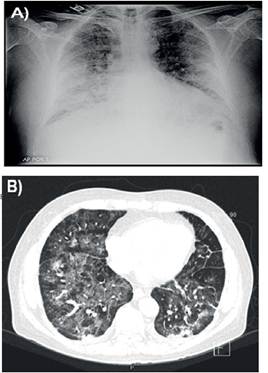

Se realiza tanto radiografía de tórax así como tomografía computada de tórax (TC-Tx) donde se observan infiltrados pulmonares con patrón en vidrio esmerilado alternado con áreas de menor atenuación con patrón en empedrado, zonas de engrosamiento septal de aspecto reticular con predominio en postero-basales, afectación panlobar y presencia de pequeñas atelectasias bibasales (Ver Figura 1 A y B).

A) Radiografa tórax AP al ingreso B) Tomografia axial con ventana pulmonar al ingreso

Figura 1:Imágenes radiológicas del paciente a su ingreso hospitalario.